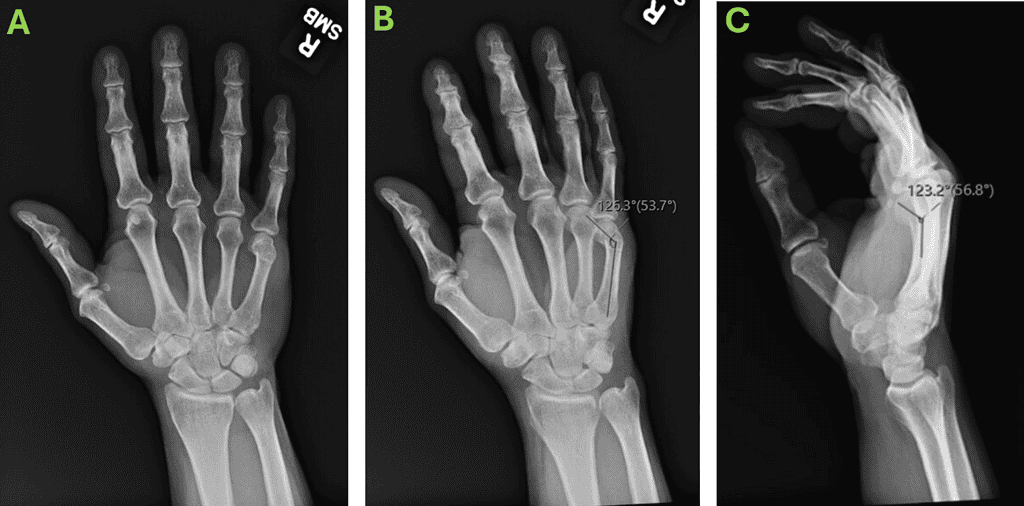

First Post-Operative X-Rays At 10 Days: Ap [A], Oblique [B] And Lateral [C].

Figure 2: First post-operative X-rays at 10 days: AP [A], Oblique [B] and Lateral [C].

Patient regained full ROM by the first post operative visit at 10 days. No pain meds needed. Patient presented excellent grip strength at 4 weeks. Due to immediate excellent stability and rotation control, no splint given, protected for 4 weeks to 2lbs but no restriction after 4 weeks (normally restriction until 6-8 weeks post ORIF needed).